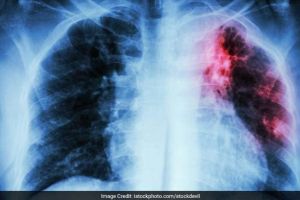

Două mari companii farmaceutice au ajuns la o înţelegere cu peste 25.000 de reclamanţi

www.tion.ro - Timiş

Două nume importante din industria farmaceutică, cărora le-au fost intentate peste 25.000 de procese, au decis să cadă la un acord cu utilizatorii nemulţumiţi, oferindu-le aproape 1 miliard de dolari pentru a-şi retrage acuzaţiile.